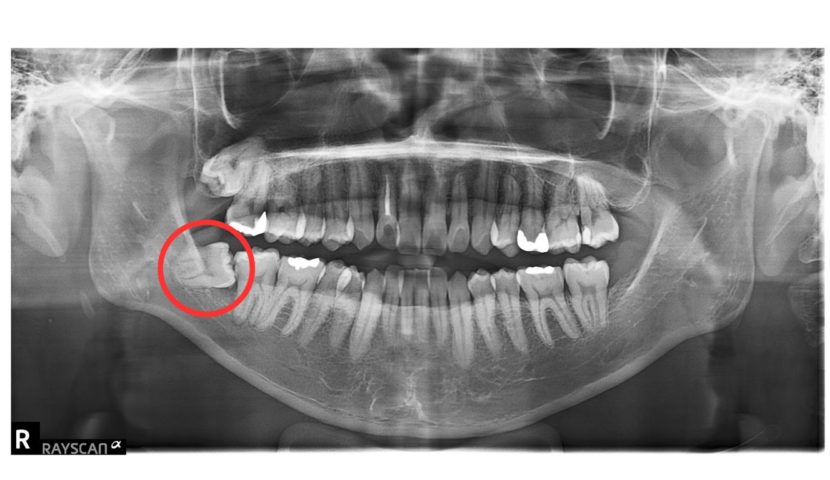

インプラント治療は、近年長期安定性が見込める治療になってきました。10年予後が下あごで99%、上あごで96%とも言われております。当院では、過去に歯を失ってしまって後悔されている方に対しても、お一人お一人にとってのベストな歯科治療をご提供できるようにしております。